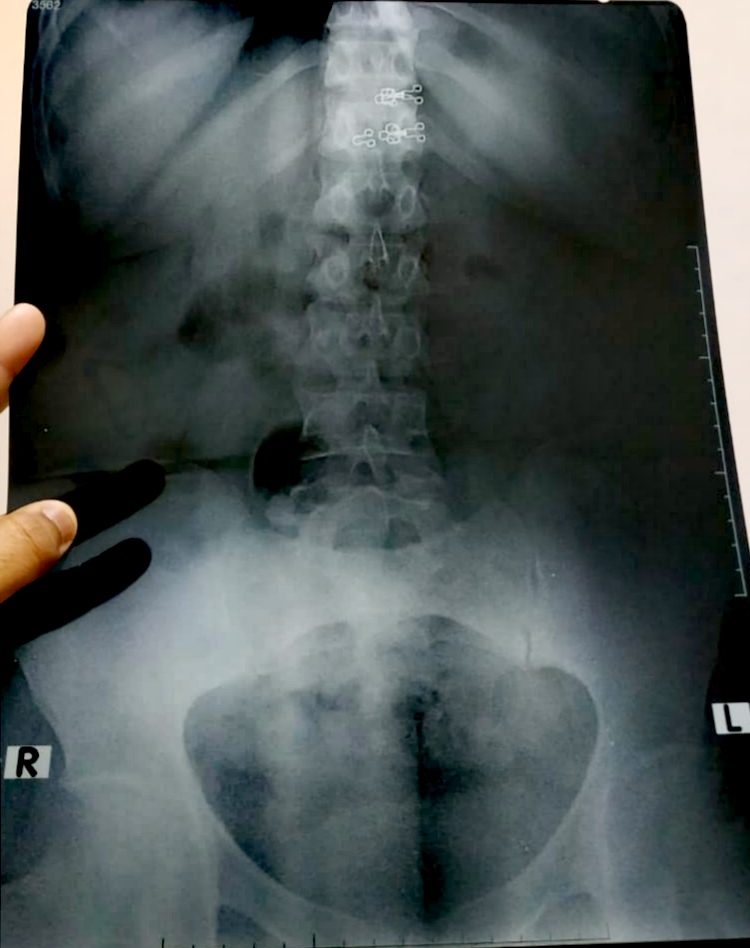

my mother is having sever pain in her lower back (the bone which joins to the hip ) she has been to doctors and have eaten the prescribed medicine but nothing seems to be working and eating these medicine make her dizzy as well . medicines she has been taking are Tonoflex Erwin 50 mg Miskoril 75 mg Pregy 75 mg methix please take a look at x ray and suggest something or really good doctor who could finally help her .please note that she is also a bp patient but her bp is normal these days .shukria

her xrays show spondylolisthesis with OA in hip and her vertebras. without treating spondylolisthesis, her pain will not go away since no medication can treat that. in Chicago USA we have been treating this successfully for over 22 years.

The quality of uploaded xrays is not clear though I do not see anything serious in these xrays.